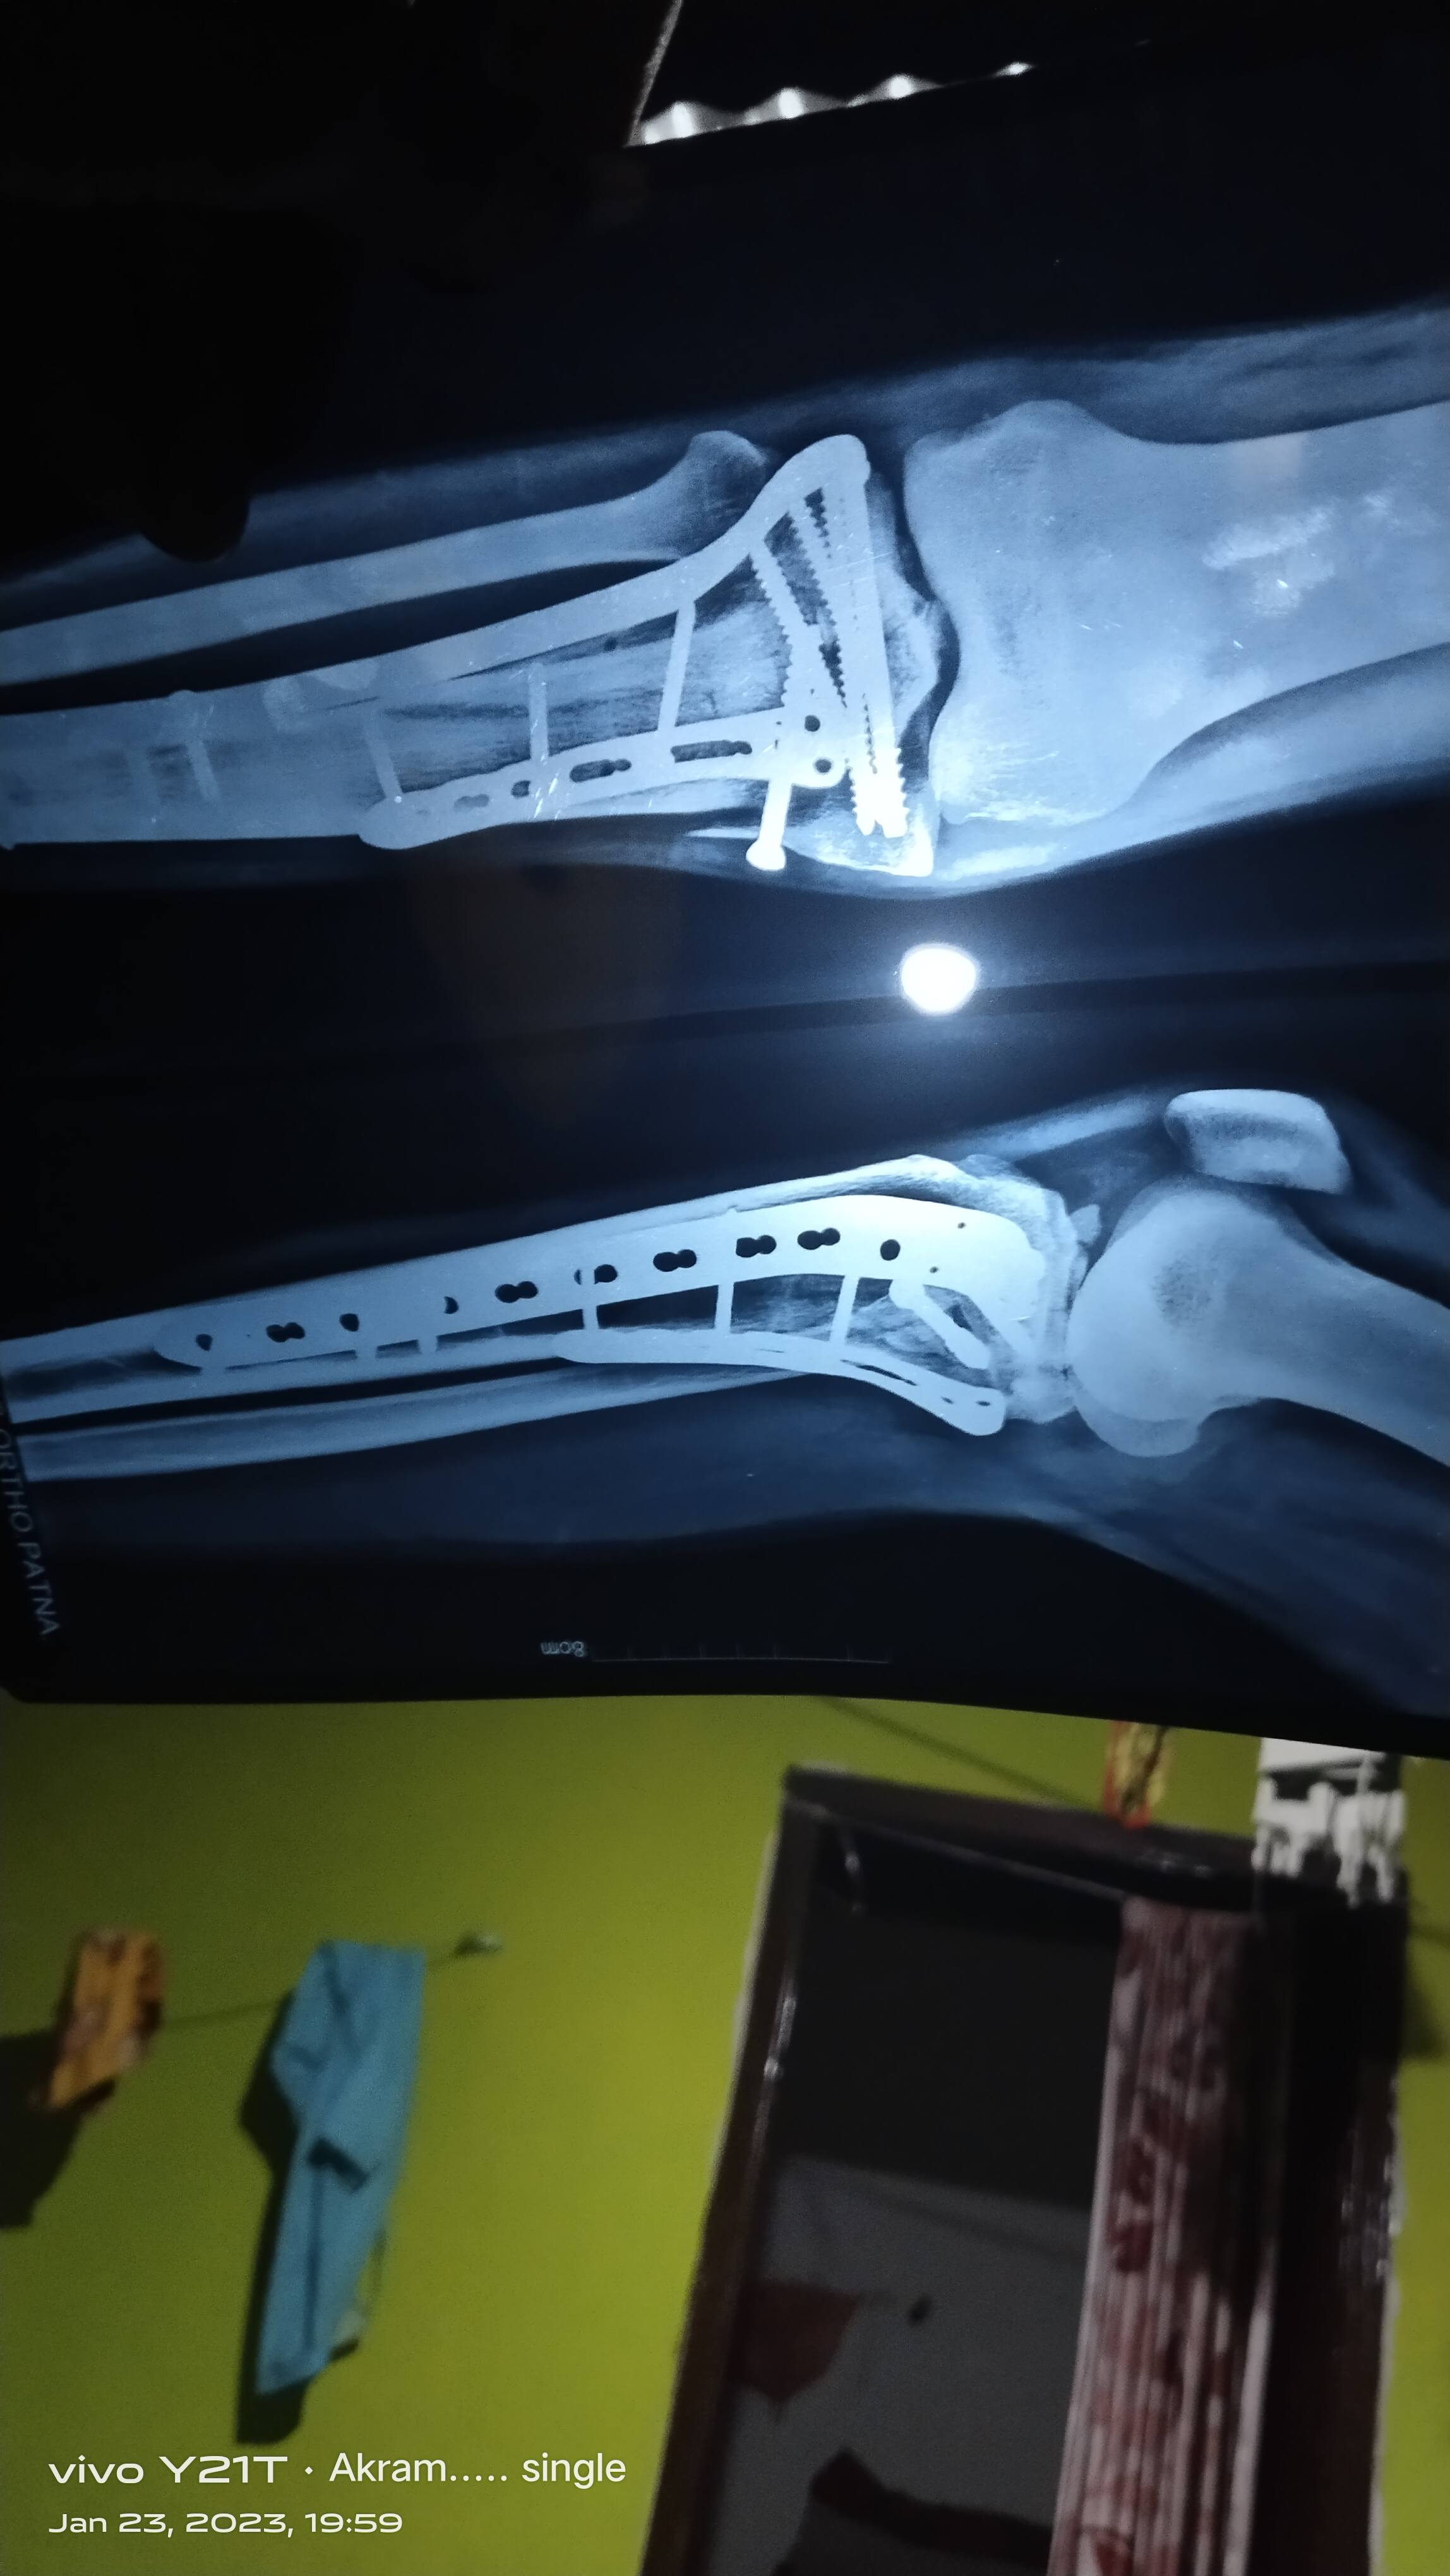

Dear sir 4.5 mahine ke baad dr. Ab kah raha hai ki isme haddi ka burada dalega dusre dr. Bhi ye kah rahe ki kulhe ki haddi nikal kar isme dalni padhegi ya phir ye jo febula bone judh gayi hai isko dobara broke karna padhega aur tibia bone ka dobara treatment karna padhega 2 solution bata rahe hai kya ye plate haddi ko nahi judhne de rahi ya koi aur baat hai febula to judh gayi tibia ka kya kiya jaye ya phir ye tablet khane se thik ho jayegi

Sir ji bone grafting ke alawa koi dusra upay DR. Ka kahna hai ki isme rod bhi nahi dhal rahi hai

isme bone grafting karna accha option hai aur plate judne se rok rahee hai . ho sakta hai plate ko bhee change karna pade